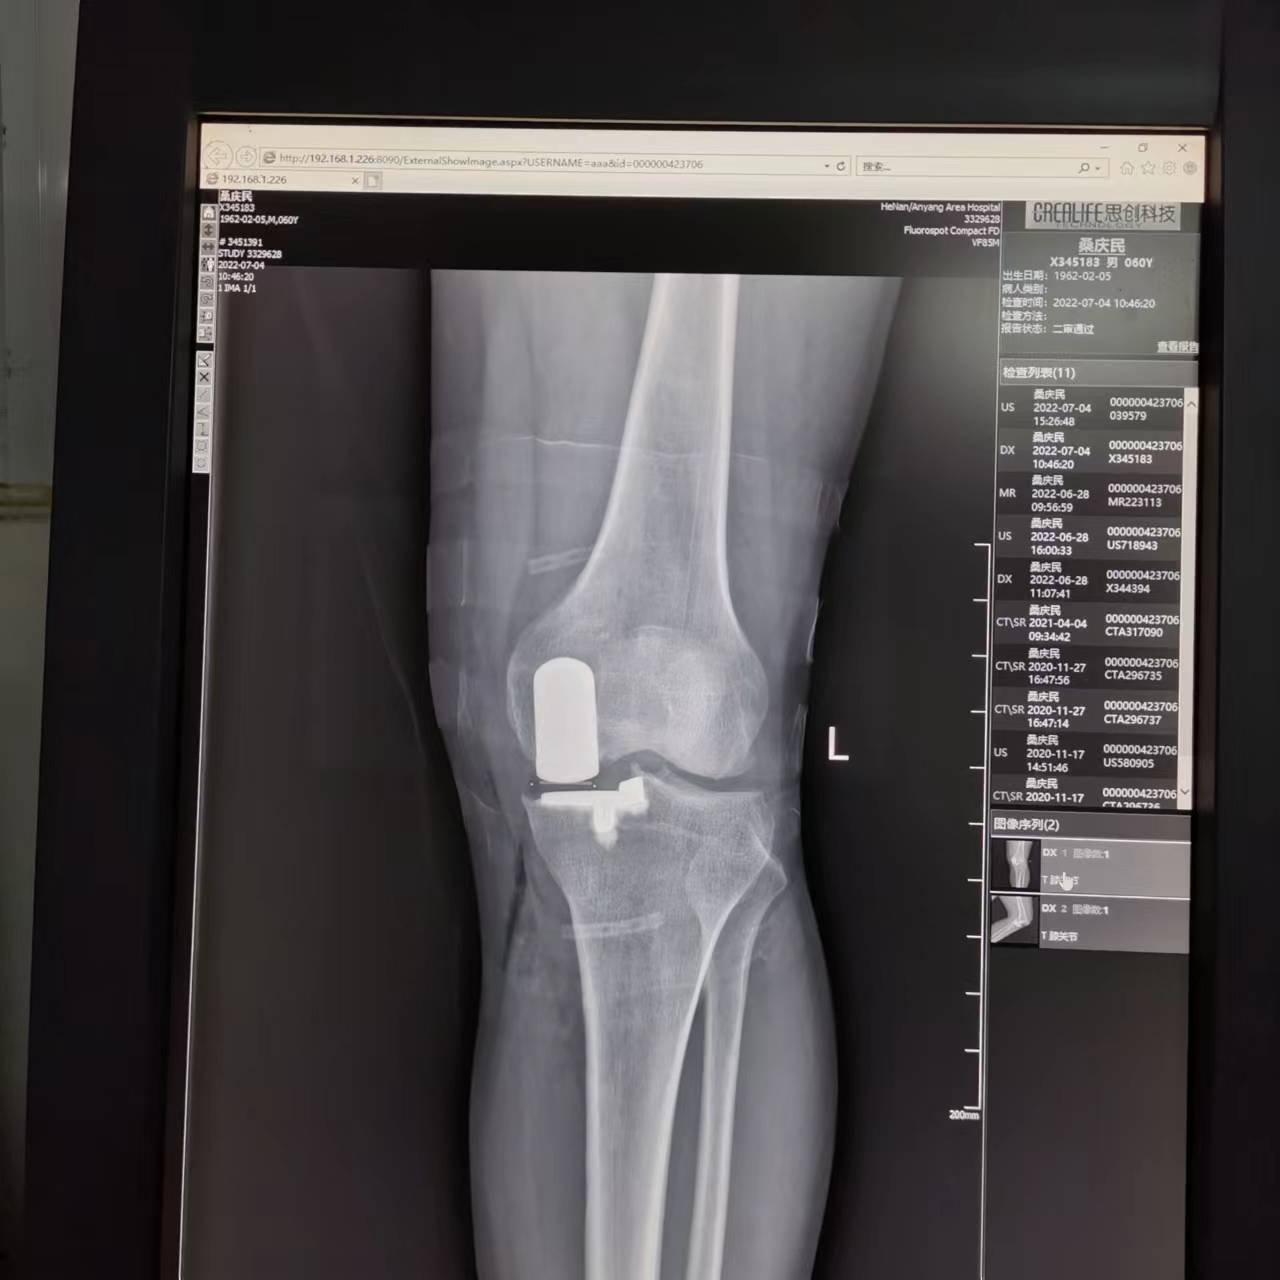

C、关节假体不同:

2、全膝置换:全膝置换是针对整个膝关节进行置换,包括胫骨平台、股骨远端部位等,所以假体相对较大,患者术后关节活动的自如度略小。